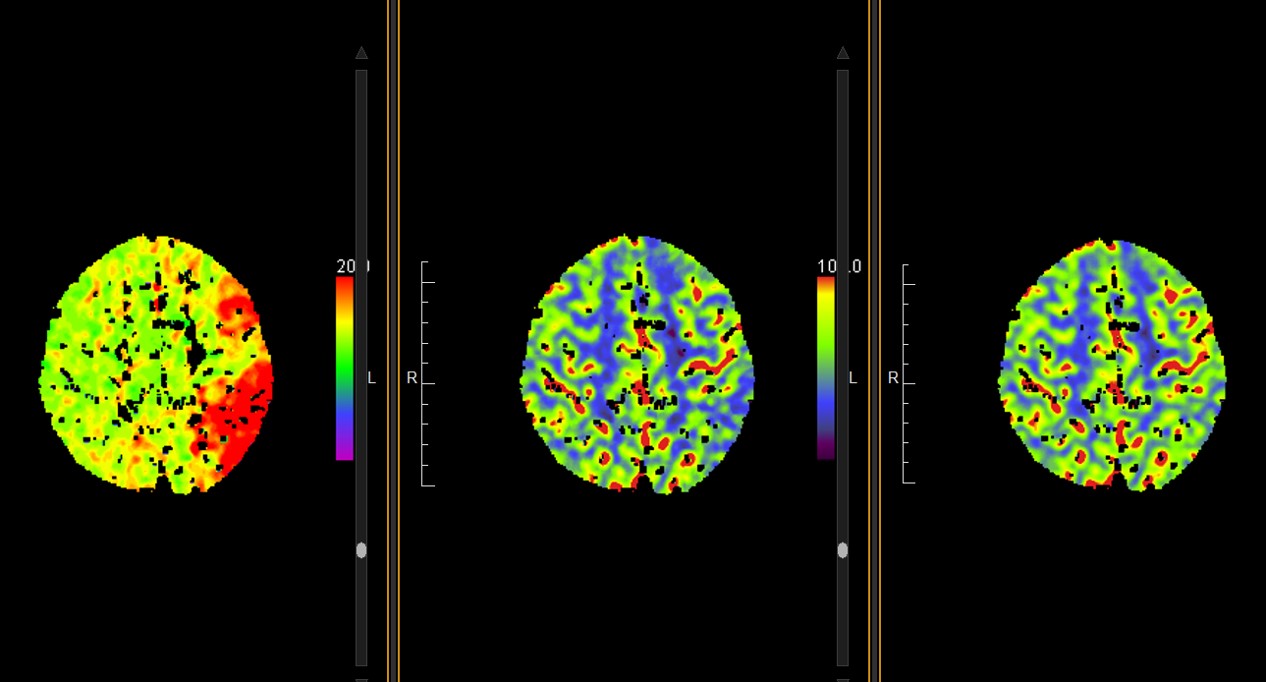

TC PERFUSIÓN: Se visualiza aumento del TTP a nivel frontoparietal, insular y lenticular izquierdos, con disminución del CBV y CBF de predominio insular y lenticular izquierdo. Hay discordancia significativa.

A su llegada a nuestro centro se encuentra hemodinámicamente estable, febricular a 37.7ºC. En la exploración neurológica presenta un sdíndrome hemisférico izquierdo extenso, NIHSS 23 (sin cambios clínicos significativos a pesar de haberse completado la fibrinolisis). Se realiza analítica sanguínea que no muestra alteraciones, el ECG se encuentra en ritmo sinusal sin alteraciones de la repolarización. Se realiza un TC craneal multimodal en que se objetivan signos de isquemia incipiente a nivel insular izquierdo sin hemorragia (ASPECTS 9); en el angioTC se aprecia una oclusión en el segmento M1 distal de la ACMI; los mapas de perfusión muestran un retraso en el territorio cortical de la ACMI con caída de volumen frontal y mismatch  significativo. Se procede entonces a realizar arteriografía, que confirma la oclusión a nivel de la bifurcación superior de la ACM izquierda. Tras varios intentos infructuosos de repermeabilización, se produce la perforación arterial de un segmento M2-M3 debido al movimiento del paciente durante el procedimiento, por lo que se decide interrumpir el procedimiento en ese momento, cuando el paciente sigue presentando oclusión arterial completa. El TC dual de control no mostró complicaciones hemorrágicas a ese nivel. Tras el procedimiento, el paciente persiste neurológicamente sin cambios.